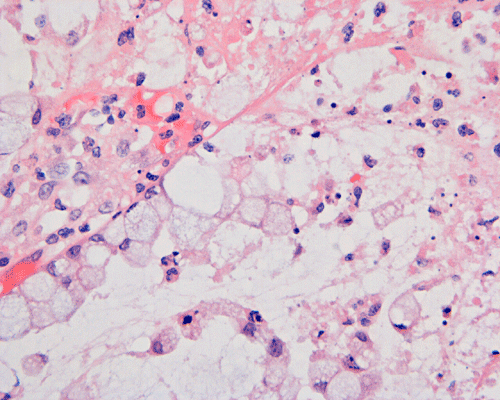

Histopathology: On scanning magnification, the mucosa has a sandwich like structure (Panel A). At the bottom is a layer of partially destroyed glands with a middle layer of mucoid material and topped by a layer of inflammatory exudate (Ž in Panel A). In some areas, the inflammatory exudate takes the shape of a mushroom or volcano (Panel B). The submucosa is edematous but lacks significant inflammatory cell infiltration. The top layer of inflammatory exudate is composed exclusively of degenerated polymorphonuclear leukocytes (Panel C and D). At the base of the mucosa, the outline of the normal glandular architecture is maintained but there is intense infiltration by polymorphonuclear leukocytes in the lamina propria (Panel E and F). On high-magnification, the crypts are filled by signet ring cells. In severely inflammed areas, there are some single singnet ring cells in the lamina propria (Panel G). In the deeper part of the mucosa where inflammation is not as intense, the boundary between the crypts and the lamina is respected by the signet cells (Panel H). In the more superficial part of the mucosa, the glandular architecture is disrupted (Panel I). Sporadic signet ring cells are also found in mucosa that are relatively unaffected (Panel J).

In this particular case, the most important clue is that the signet ring cells distribute within the crypt and respect the anatomic boundaries. Focally, this boundary is blurred by inflammatory cell infiltration in some areas and these areas should not be mistaken as evidence of invasion. Signet ring cells have a tendency to invade as single cells or small clusters of few cells in areas away from larger tumor cell clusters. This feature is also lacking in this case.

While there are general features which can be used to differentiate benign signet-ring cell changes from signet-ring cell carcinoma on hematoxylin and eosin stained sections, well-differentiated signet-ring cell carcinoma may be more difficult to exclude. General features which can be used to define benign signet-ring cell changes are the absence of infiltration of signet ring cells into the lamina propria and bland cytologic features. Extensive signet ring cells may be noted within the crypts and the inflammatory exudates. 6, 9. Infiltrating signet ring cells in a location remote from the main bulk of signet ring cells raises a strong suspicion of signet ring cell carcinoma. Immunohistochemistry for cytokeratin and, to a less extent, mucicarmine stain are helpful in demonstrating these clusters.